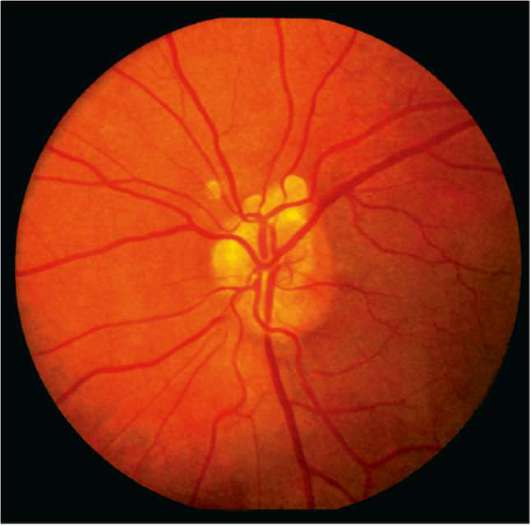

Атрофия зрительного нерва Лебера: Симптомы и лечение